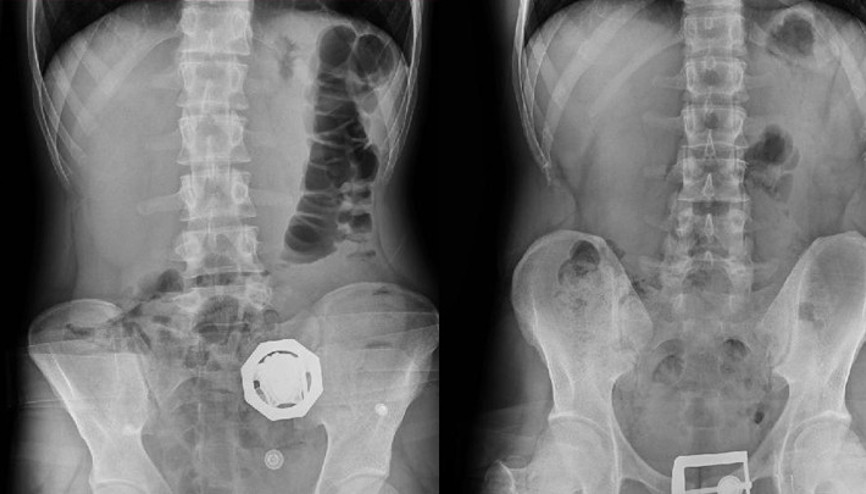

#Ali YerlikayaKONYA’da polisin bir eve düzenlediği operasyonda, İran uyruklu Vahıd Farhang Gangachı'nın (33) ile 4 kişi gözaltına alındı, 1 kilo eroin ele geçirildi. Uyuşturucu kuryeliği yapan ve İran’da iş insanı olduğu belirlenen Gangachı, yuttuğu 300 gram eroini ise hastanede doğal yollarla çıkardı. 5 şüpheli, çıkarıldığı mahkemece tutuklandı.